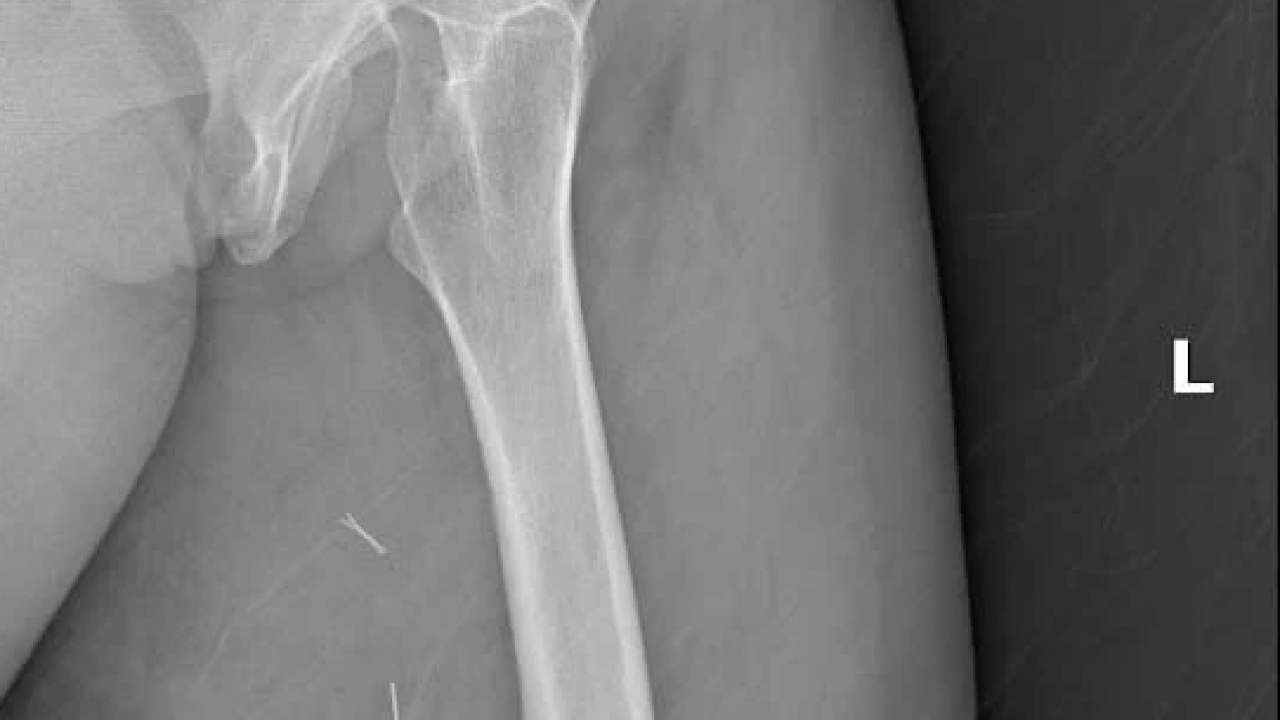

Diyarbakır Dicle Üniversitesi Hastanesi’nde, Mardin’den gelen H.T. isimli kadının bacağından 5 kilo 668 gramlık bir kitle çıkartıldı. Ameliyatı gerçekleştiren Prof. Dr. Emin Özkul meslek hayatındaki çıkarttığı en büyük kitle olduğunu söyledi.

Mardin’de yaşayan H.T. (42), 3 yıl önce sağ baldırının arka kısmında oluşan ve başlangıçta yumurta büyüklüğünde olan kitlenin zamanla büyümesi üzerine Dicle Üniversitesi Tıp Fakültesi Hastanesi Ortopedi ve Travmatoloji Bölümü’ne başvurdu. Muayenede yumuşak doku kitlesi olduğu değerlendirilen şişliğin alınması için Ortopedi ve Travmatoloji Anabilim Dalı Öğretim Üyesi Prof. Dr. Emin Özkul ve ekibi tarafından ameliyat kararı verildi. Yaklaşık 2 saat süren operasyonla kitlenin çıkarıldığı, kitlenin 5 kilo 668 gram geldiği belirtildi.

"Bu hasta da 3 yıl önce fark edilmiş küçük bir kitle, zamanla çok büyük boyutlara, yaklaşık 6 kiloya varan boyutlara varmıştı. Neredeyse bütün bacak boyu yayılan bir kitlesi mevcuttu. Bu kadar büyümenin şöyle sıkıntıları oluyor, kişinin bacağında, kolunda fonksiyon kaybına, yeri geliyor ekstremite kaybına, yani bacağını kaybetmesine yol açabilecek sıkıntılara yol açıyor."

"Küçükken bunlarla baş etmek daha kolay. Kişinin ekstremitesinde, bacağında, kolunda bir sıkıntı yaratmadan bunları telafi etmek, bunları alıp çıkartmak, ameliyatla bunları tedavi etmek daha kolayken bu boyutlara vardığında kişinin bacağında, kolunda fonksiyon kaybı, sakatlık riski çok yüksek oluyor. Bu sebeple küçükken önleminin alınmasında yarar var.” “Hastamızda yaklaşık olarak 3 yıl önce şikayetleri başlamış. Sonra zaman içerisinde hızla büyüyen bir kitleye sahipti. Şanslıydı ki herhangi bir sinirine zarar vermemişti. Hayatına fonksiyon bozukluğu olmadan devam edebilecek. Bölgemize yaşayan ve ülkemizde yaşayan herkese şunu söylüyoruz. Küçük de olsa yumuşak doku kitlelerini önemsemeleri ve uzman görüşü almalarını öneriyorum. Bu hastadan 5 kilo 668 gramlık bir kitle çıkarttık. Bu benim mesleki yaşamım boyunca çıkarttığım en büyük kitlelerden bir tanesiydi. Biraz daha büyük boyutlara varmış olsa kişinin bacağını kurtarma şansınız olmuyor. Bu sebeple bunlara dikkat etmek gerekiyor. Hızlı büyüyen bir kitleniz var ise, ağrısız da olsa mutlaka ve mutlaka tedavi için en yakın sağlık kuruluşuna veya bizim üniversitemizin polikliniklerine başvurabilirsiniz.”